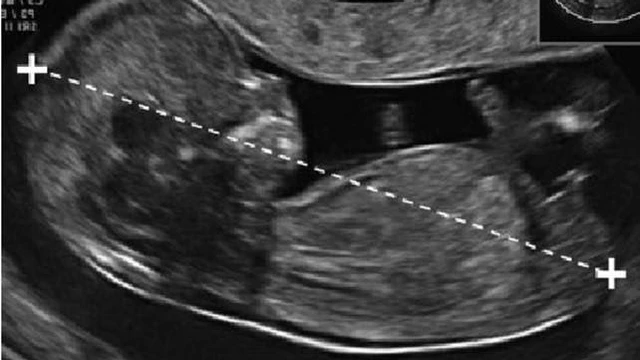

Kết quả đo độ mờ da gáy cao nhưng chọc ối bình thường có thể xảy ra trong một số trường hợp. Việc đo độ mờ da gáy chỉ cung cấp thông tin một phần, và đôi khi nó có thể không phản ánh đúng tình hình của thai nhi. Trong trường hợp này, bác sĩ sẽ tiếp tục theo dõi và đánh giá sự phát triển của thai nhi bằng cách sử dụng kết quả chọc ối để đưa ra đánh giá tổng quan về tình hình sức khỏe của thai nhi. Hãy cùng Nhà thuốc Long Châu tìm hiểu về trường hợp này nhé!

Siêu âm đo độ mờ da gáy là một trong các phương pháp xác định nguy cơ mắc dị tật ở thai nhi mà mẹ cần làm. Vậy siêu âm 2D có đo được độ mờ da gáy không? Vấn đề đó sẽ được giải đáp qua bài viết sau đây.

Đo độ mờ da gáy là một trong những bước quan trọng nhằm xác định nguy cơ bị bệnh Down ở trẻ nhỏ. Vậy nguyên nhân độ mờ da gáy cao ở bé là gì? Hãy cùng chúng tôi tìm hiểu lý do đó qua bài viết sau đây nhé.